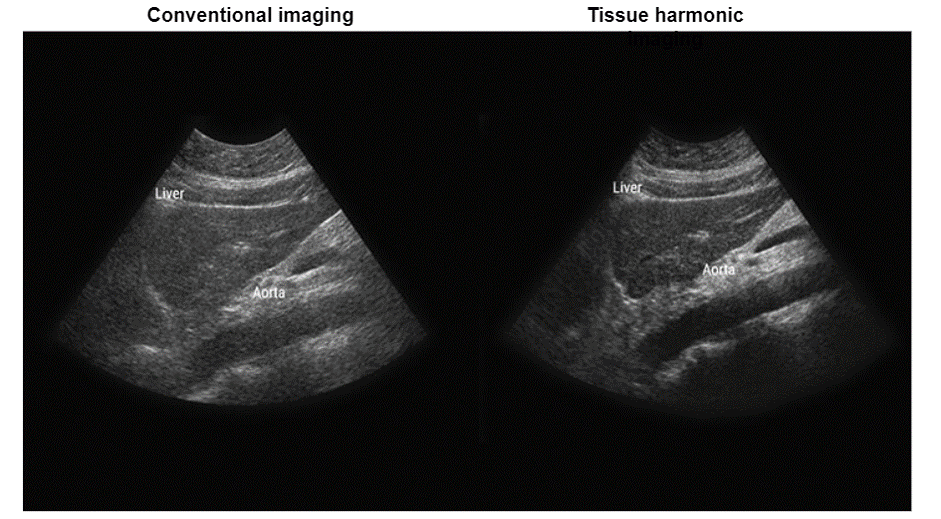

As we mentioned previously, the transmitted pulse consists of a range of frequencies centered around f0. In a linear medium, the echo pulse frequency is the same as the fundamental frequency but has lower energy, whereas the nonlinear medium results in harmonic waves of higher frequency and lower energy as shown in this figure. It is important to note that the majority of clinical US systems use second harmonic (ie, 2f0) echoes for THI image formation.

Now, let’s go deeper and explain the fundamental wave elimination techniques. The fundamental and the second harmonic frequencies are received together in the time domain as a combined distorted wave. High-quality THI primarily depends on the achievement of the complete elimination of the echoes at the fundamental frequency. Various techniques are used to remove the fundamental wave in THI, including bandwidth receive filtering, pulse inversion, side-by-side phase cancellation, and pulse-coded harmonics.

Bandwidth receive filtering is a signal processing technique in which lower frequencies that are more likely to have emerged from the fundamental beam are filtered out, and higher-frequency harmonic echoes are used to generate the image. In this technique, noise such as reverberation artifact and tissue aberrations diminishes and enhancement is improved.

Clinical Advantages

The advantages of harmonic imaging include, but are not limited to improved signal-to-noise ratio and reduced artifacts, or better axial and lateral resolutions due to higher frequencies and narrower beams.